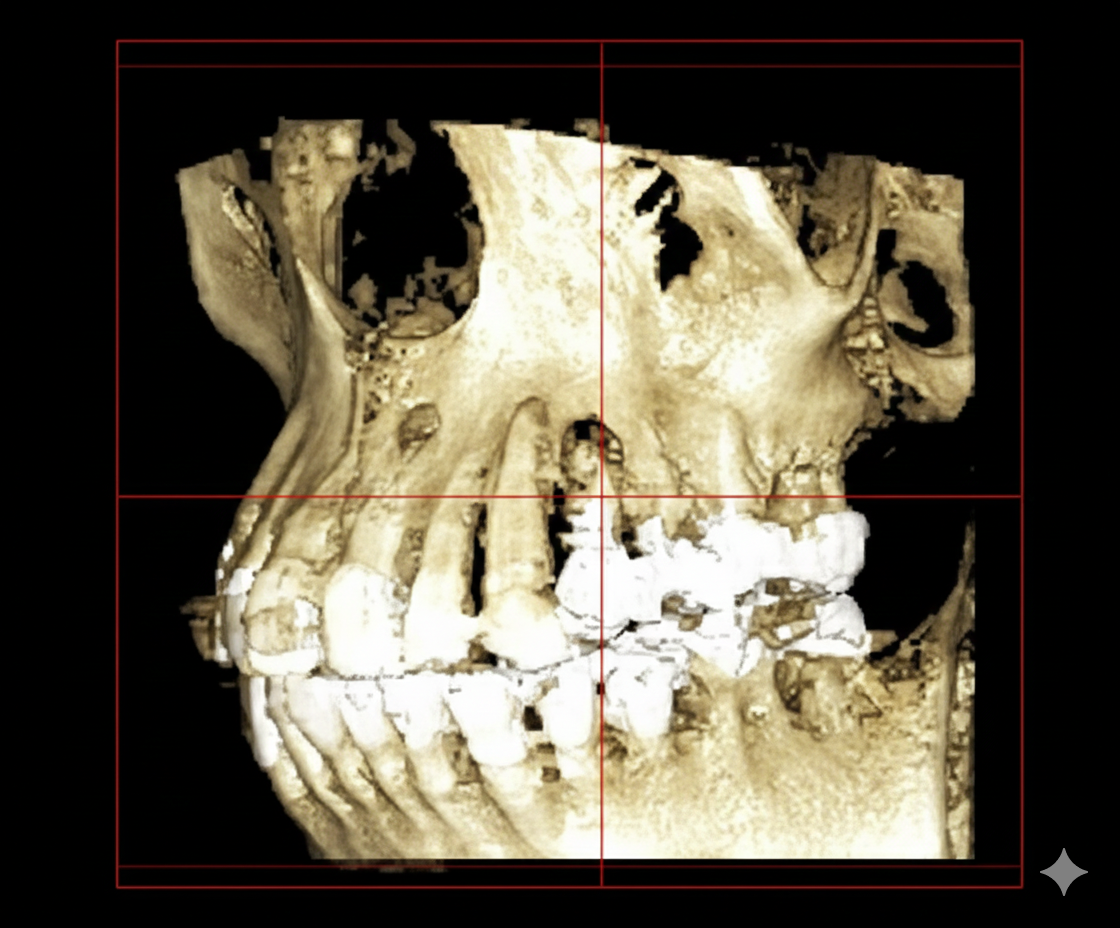

従来のレントゲン画像は平面像(二次元)でしたが、歯科用CT画像は立体画像(三次元)でみることが出来ます。

ですから、インプラントや歯周病などの診断に有効で、従来の平面画像では難しいとされた骨の幅の確認などが行えます。CT撮影で様々な角度から診断することで、正確な診査・診断に役立ち、より安全で確かな治療を行うことが可能となります。

インプラント治療では、CTの画像から埋入する部位の骨の状態(質や厚み、高さ、形態など)を正確に読み取り、そこから治療計画を立てることが出来ます。歯科用CTでの撮影画像をもとに、的確な治療計画を立てることは、安心な治療への第一歩です。また三次元の立体画像から、神経などを避けた安全な位置、方向、深さを決定し埋入する事が可能となり、より安心・安全な治療を提供する事が出来ます。

歯科用CTを親知らずの抜歯に利用することで、神経までの正確な距離や、周囲の炎症の程度、病巣の有無や大きさ、位置なども判断・考慮して、治療を行うことができます。また埋伏歯などの位置なども精密に判断できるので、余分な切開や骨の切削などを避けることができます。